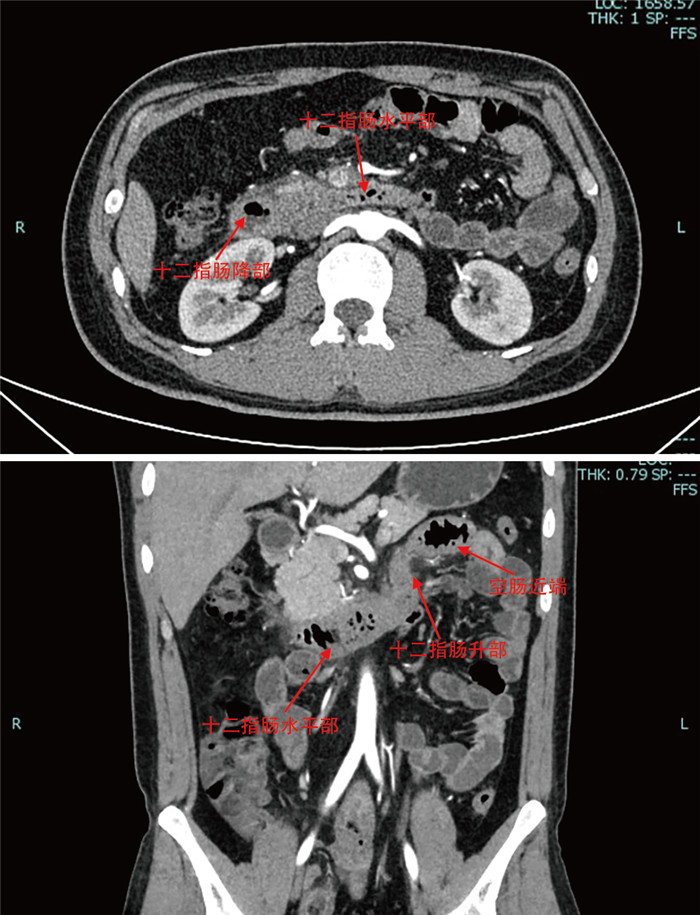

Construction and verification of prediction model and treatment strategy for shunt loss after portal hypertension TIPS

QIAN Jinyu, YANG Peipei, ZHANG Yang, XIE Bo, WU Di, TANG Xiaoyun, ZHANG Leiming, TAN Yulin, ZHANG Zichen

2025, 23(7): 1107-1110. doi: 10.16766/j.cnki.issn.1674-4152.004075

429 3

Abstract:

Objective   To identify the risk factors of shunt dysfunction after transjugular intrahepatic portosystemic shunt (TIPS) in patients with portal hypertension, to construct and verify the clinical prediction model, and to formulate corresponding countermeasures for different types of shunt dysfunction, so as to provide reasonable treatment for patients.   Methods   The clinical data of 120 patients who underwent TIPS in the interventional department of the First Affiliated Hospital of Bengbu Medical University from January 2020 to December 2024 were retrospectively analyzed. Subsequent to the surgical procedure, the subjects were categorized into two distinct groups, namely the shunt dysfunction group and the non-dysfunction group, with the respective numbers amounting to 35 and 85 cases. Variables with significant differences were included in multivariate logistic regression analysis to determine the independent risk factors, and a prediction model was constructed based on this. The discrimination capacity of the model was evaluated by means of the ROC curve. Finally, the corresponding countermeasures are proposed for the various types of shunt failure.   Results   Multivariate logistic regression analysis demonstrated that anticoagulation therapy (OR=15.754, P=0.030), portal vein thrombosis (OR=0.052, P=0.008) and portal vein puncture site (OR=0.064, P=0.007) were independent influencing factors for shunt dysfunction after TIPS. The area under the ROC curve (95% CI) of the constructed model was 0.933 (0.882-0.983), and the corresponding optimal cut-off value was 0.866. The sensitivity was 0.894, and the specificity was 0.971.   Conclusion   Therapy, portal vein thrombosis and portal vein puncture site are independent influencing factors of shunt dysfunction after TIPS. The prediction model constructed accordingly has the potential to assist clinicians in the early identification of risks and the implementation of intervention measures.